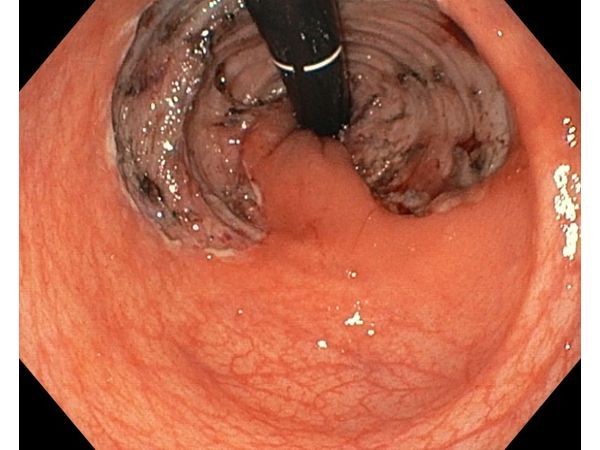

Спустя год провели контрольную колоноскопию и КТ. Рана в области вмешательства полностью зажила, сформировался белый рубец, который не мешал опорожнять кишечник. Признаков рецидива и вторичного поражения соседних органов не было.